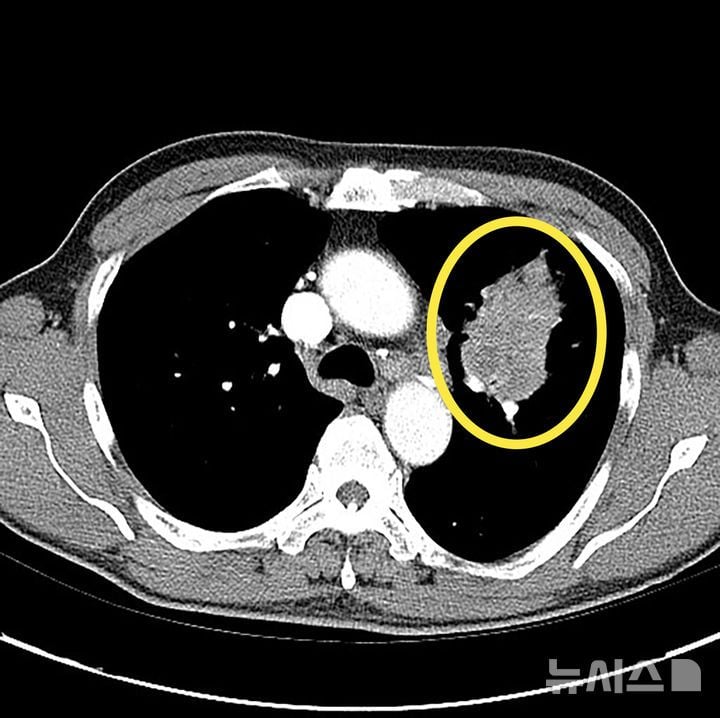

폐암은 폐 조직에 악성 종양이 발생하는 질환으로, 세포 형태에 따라 비소세포폐암과 소세포폐암으로 분류된다. 전체 환자의 85%를 차지하는 비소세포폐암은 비교적 진행이 느린 편이지만, 소세포폐암은 급속도로 전이돼 치료 시기를 놓치기 쉽다. 지난해 기준 폐암 환자의 5년 상대생존율은 40.6%에 그쳤지만, 조기 단계에서 진단 시 79.8%까지 상승한다는 점은 진단 시점이 치료 성과에 반드시 작용함을 시사한다.

문제는 폐암이 초기에 특별한 증상이 거의 없다는 점이다. 기침, 가래 등도 감기와 혼동하기 쉽고, 폐 조직 자체가 통증을 잘 느끼지 않기 때문에 상당히 진행된 후 발견되는 사례가 다수다. 증상이 없는 상황에서 건강검진이나 타 질환 검사를 통해 우연히 진단되는 경우가 일반적이다. 그러므로 흡연력 30갑년 이상, 55세 이상, 가족력이나 환경 노출 등 고위험군은 반드시 정기적으로 검진을 받아야 한다는 권고가 강화되고 있다.

진단 기술은 최근 저선량 흉부 CT가 핵심 도구로 자리잡는 중이다. 초기 폐결절을 감지하는 데 기존 흉부 X-레이보다 월등히 정확하며, 이상 소견이 발견되면 조직 검사 및 분자유전학적 검사로 암세포의 유전자 변이 여부까지 확인한다. 이렇게 축적된 데이터는 환자별 맞춤 치료제 선택과 적용에 직접 연계된다.